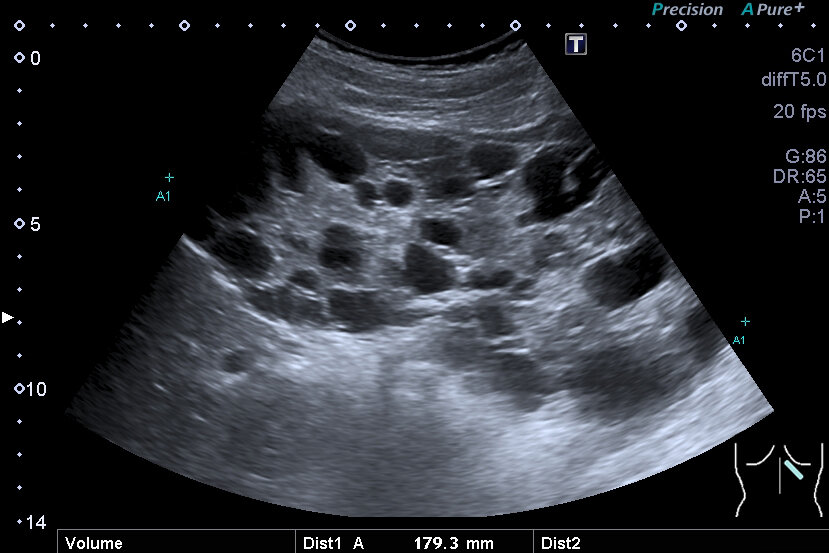

Sehr große, zystisch umgebaute Niere bei autosomal dominant vererbter polyzystischer Nierenerkrankung mit Hypertonie bei einem Jugendlichen. (Foto: Roselieb)